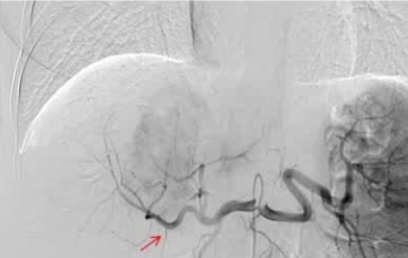

· 单中心、样本量小; 83 岁的女性,体重超标 40 毫米单发 ICC(S7-S8) 中肝静脉和右肝静脉浸润性,活检:非酒精性脂肪性肝炎(慢性肝病),马斯氏(MaS)病(30%)

考虑采用“三步策略 TARE→ PVE → Surgery”方案 剂量活性:1.56 和 3.16 GBq